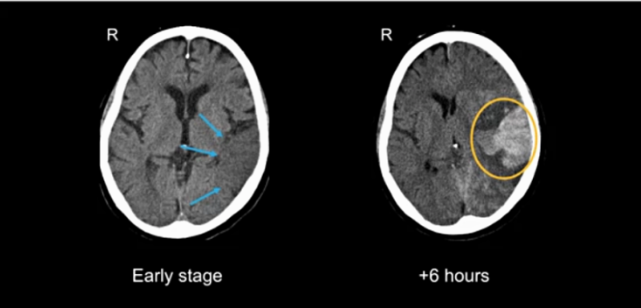

뇌경색 골든타임과 일과성 허혈성 발작의 경고

뇌세포는 혈액 공급이 중단되는 순간부터 급격히 괴사하기

시작하므로 뇌경색 골든타임을 지키는 것이 생존의 핵심입니다.

의학적으로 권고되는 정맥 내 혈전용해제 투여 시간은

증상 발생 후 4.5시간 이내입니다. 이 시기를 놓치지 않아야

뇌 손상을 최소화하고 마비나 언어장애 같은

심각한 후유증을 방지할 수 있습니다.